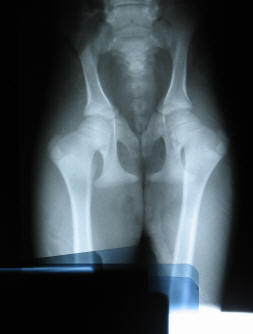

The diapers did exactly what I needed them to do. They held her rear legs together to kept her from doing the "splits" yet still allowed her to mover her legs forward and back in the correct walking and trecking motion. I taped a sling on her so I could help her get up and down and I supported her weight on short walks to insure the proper development of her muscles. Diva and Eve stayed in my house with me "sleeping" on the couch next to Diva for 2 weeks. Diva was never left unattended because one slip could ruin her chances of ever walking on her own. I was banking on the fact that crias are born limp and limber. That Diva could compensate for the tendons and ligaments that had been torn during her birth by over firming the ones that had been abnormally stretched, as her body went through it's normal process of firming up after birth. It was only by divine design that after 2 weeks of Diva's birth, she could get up and down by herself, walk without support and had proved that she was tightening up because she was able to keep her legs together on her own without the diapers. Hence her name, BiDevine Design. Diva wore the diapers for a total of 2 months and was very restricted on her activities. She stayed with Eve in a 12 x12 stall with 5 minutes twice a day of "free time" in the 30 x 60 barn hallway. She quickly got the nick name of "Speed Racer" since she would use that time wisely and race up and down the hallway nonstop till I caught her and put her "back in jail". Her free time was increased by 5 minutes each time she showed signs of becoming stronger. I had to be careful and pray that she did not have any accidents while playing for she was getting past the point where her cria body could naturally compensate from a birthing trauma. Today, there is not even a hitch in her step. She trecks as smooth as the best of them and we can not wait to get her into the show ring. We do however, plan to have her OFA'd at 2 years of age before breeding her. I know her problem was due to injury but I do not want any question as to her conformation or her ability to safely bear her own crias.